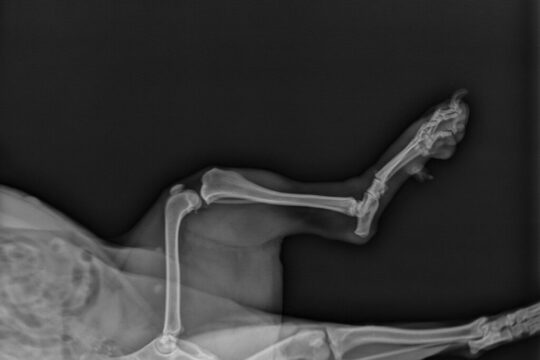

La luxación de rótula es una lesión común en los perros, especialmente en razas pequeñas y de juguete. Esta afección ocurre cuando la rótula se desplaza fuera de su posición normal en la articulación de la rodilla.

Una vez que se haya diagnosticado la luxación de rótula, el siguiente paso es evaluar el grado de la lesión. Esta afección se clasifica en diferentes grados, desde leve hasta grave. El veterinario determinará el grado de luxación y recomendará el tratamiento adecuado.

La luxación de rótula es una condición común en perros, especialmente en razas pequeñas y de juguete. Esta condición ocurre cuando la rótula, que es el hueso sesamoideo que articula la rodilla, se desplaza de su posición normal. La luxación de rótula puede ser causada por diversos factores, como malformaciones congénitas, trauma o debilidad en los tejidos que mantienen la rótula en su lugar.

La luxación de rótula es una afección común en los perros, especialmente en razas pequeñas y de juguete. Se refiere a la dislocación o desplazamiento de la rótula, el hueso triangular que se encuentra en la parte delantera de la rodilla.